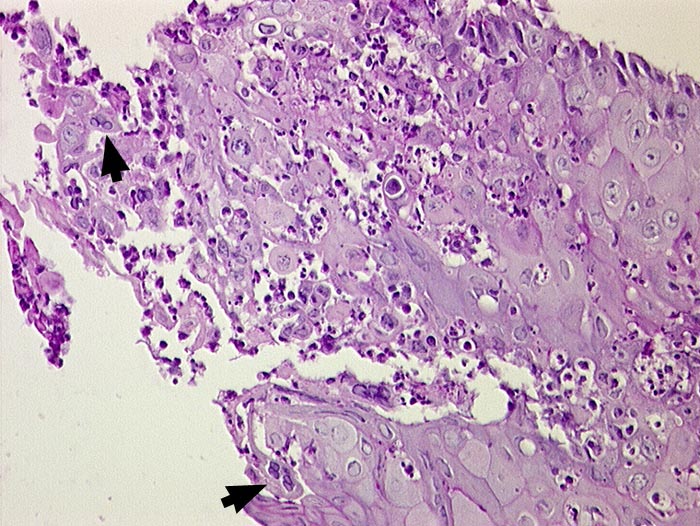

PathoPic ID 1478 - Akute Herpesösophagitis

Akute Herpesösophagitis

Entzündung infektiös

Oesophagus

Oberflächliche Epithelzellen mit Milchglaskernen, teilweise

►

mehrkernig. Granulozytäres Entzündungsinfiltrat.

Immunhistochemisch HSV Antikörper positiv.